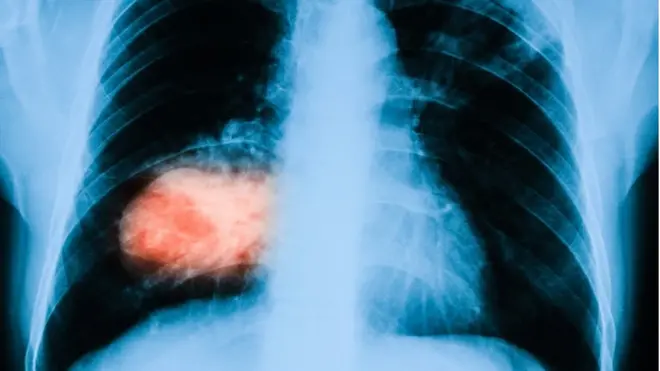

د عکس سرچینه، Getty Images

د چاغښت او پر سالنډۍ د اخته کېدو یا د هغې د نښو زیاتوالی پېژندل شوې خبره ده. په څېړل شوېو نمونو کې ښودل شوي چې ۱۵ کسانو سالنډي نه درلوده او ۲۱ کسانو هم سالنډي درلوده، خو په بل لامل مړه شوي او۱۶ کسان هم د سالنډۍ له وجې مړه وو.

له ډالۍ شویو سږو څېړونکو ۱۴۰۰ نمونې واخېستې او له رنګولو وروسته یې مایکرسکوب کې وکتلې او ویې لیدل د هغو کسانو تنفسي لارو کې چې ډېر چاغ و، ډېره وازده هم وه.

دوی متوجه شول چې وازده زیاتېدلو سره د هوا یا تنفس لارو طبیعي جوړښت بدلېږي او سږي پړسېږي چې ممکن په چاغو کسانو کې د سالنډۍ د ډېرو پیدا کېدو وضاحت وکړي.